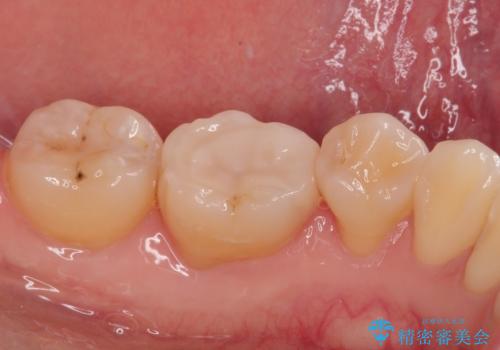

治療後、特に異常もなく見た目、噛み合わせともに満足していただけました。

ラバーダム防湿を行い、セラミックの接着をすることで、唾液や血液などの接着阻害因子を排除することができます。